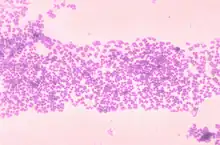

Micrococcus (mi’ krō kŏk’ Əs) is a genus of bacteria in the Micrococcaceae family. Micrococcus occurs in a wide range of environments, including water, dust, and soil. Micrococci have Gram-positive spherical cells ranging from about 0.5 to 3 micrometers in diameter and typically appear in tetrads. They are catalase positive, oxidase positive, indole negative and citrate negative. Micrococcus has a substantial cell wall, which may comprise as much as 50% of the cell mass. The genome of Micrococcus is rich in guanine and cytosine (GC), typically exhibiting 65 to 75% GC-content. Micrococci often carry plasmids (ranging from 1 to 100 MDa in size) that provide the organism with useful traits.